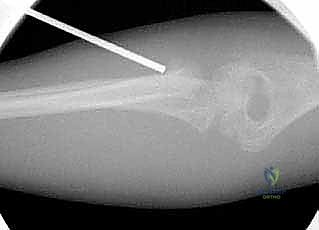

1. الرد المغلق والتثبيت عبر الجلد (CRPP - Closed Reduction and Percutaneous Pinning)

هذه هي التقنية السائدة والمفضلة عالمياً لعلاج كسور عنق الكعبرة لدى الأطفال (تقنية ميتازو Métaizeau Technique). وهي تقنية طفيفة التوغل لا تتطلب شقاً جراحياً كبيراً، مما يحافظ على الأنسجة المحيطة ويقلل من خطر الندبات وتيبس المفصل.